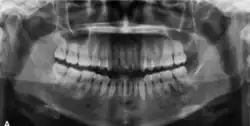

Panoramic radiograph showing a radiopaque lesion surrounded by a radiolucent rim around the root of left first and second mandibular molar [25]